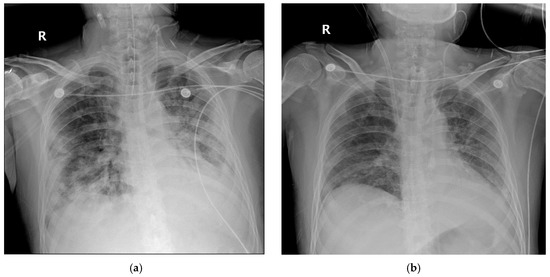

2.2. Case 2

2.3. Case 3